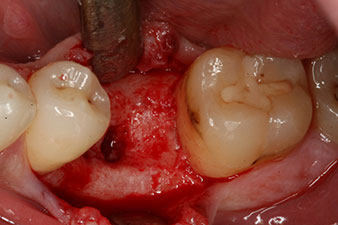

Sechs Wochen nach Extraktion zeigte sich jedoch nach Präparation des Mukoperiostlappens im Bereich der ehemaligen mesialen Alveole eine unvollständige Ossifikation.

Nach gründlicher Entfernung des Granulationsgewebes wurde das Implantat wie geplant eingebracht (blueSky, bredent).

Das Drehmoment beim maschinellen Einbringen war 43 Ncm. Zusätzlich wurde, nach Einschrauben eines speziellen, auf das Implantatsystem abgestimmten Mess-Pfostens (SmartPeg), der ISQ-Wert mit der Sonde des W&H Osstell ISQ Modul bestimmt.

Dieses Modul ist für das Implantmed von W&H optional erhältlich und wird an den Implantologiemotor gedockt (vgl. Abb. 11). Der dimensionslose ISQ-Wert war direkt bei der Insertion 64 in oro-vestibulärer und 68 in mesio-distaler Richtung (Maximalwert = 100). Dies hätte eine offene Einheilung oder sogar Sofortversorgung erlaubt.

Wegen des unzureichenden Knochens krestal am Implantat wurde der Bereich mit den bei der Präparation des Implantatlagers gesammelten Knochenspänen augmentiert und speicheldicht vernäht.